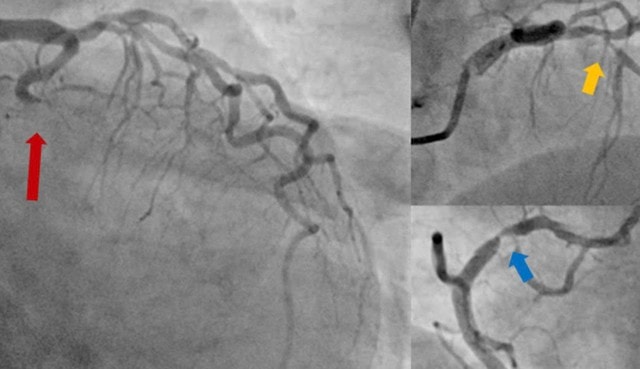

Bệnh nhân sau đó được đưa đến phòng DSA để được chụp động mạch vành cấp cứu. Kết quả chụp mạch vành cho thấy tắc hoàn toàn động mạch mũ, hẹp nặng động mạch liên thất trước và vành phải.

Sau hội chẩn, các bác sĩ nhận định: Đây là trường hợp ngưng tim sau nhồi máu cơ tim, với "thủ phạm" là tắc hoàn toàn động mạch mũ, đồng thời hẹp nặng cả hai nhánh động mạch vành còn lại.

Sau khi giải thích kỹ chẩn đoán, định hướng điều trị, các lợi ích và nguy cơ của thủ thuật cho người nhà, bệnh nhân lần lượt được can thiệp nong bóng và đặt stent thành công cả ba nhánh động mạch mũ, động mạch liên thất trước và động mạch vành phải.